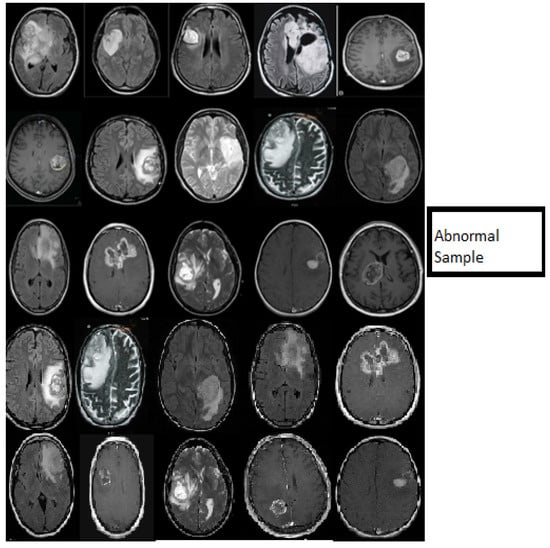

3. Datasets

- In classification, we applied a deep wavelet auto-encoder (DWAE) model. In this stage, the segmented MR brain image is resized by 256 × 256 × 1 dimension for faster processing. The objective of this stage is to predict the slices with tumor (abnormal MR brain images and the slices without tumor (normal MR brain images).